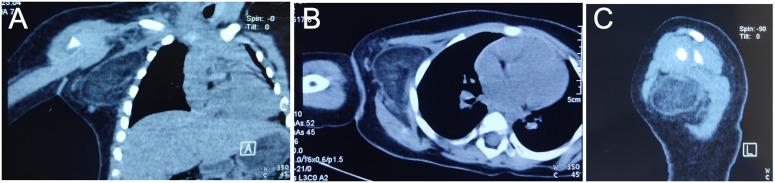

病例报告:婴儿巨大腋窝脂肪瘤。

Case Report: Giant axillary lipoma in an infant.

Lipoma is a benign mesenchymal tissue tumor, mainly composed of mature adipose cells; it is most common in adults and is rarely observed in children. The clinical data of an infant diagnosed with a giant axillary lipoma admitted to our hospital were analyzed. A 12-month-old girl presented with a large mass in the right axillary region. Imaging examination suggested a mesenchymal tissue tumor and postoperative pathology confirmed lipoma.

脂肪瘤是一种良性间叶组织肿瘤,主要由成熟脂肪细胞组成;多见于成年人,儿童罕见。对我院收治的1例诊断为巨大腋窝脂肪瘤的婴儿临床资料进行分析。一名12个月大的女童右腋窝区出现一个巨大肿块。影像学检查提示为间叶组织肿瘤,术后病理证实为脂肪瘤。